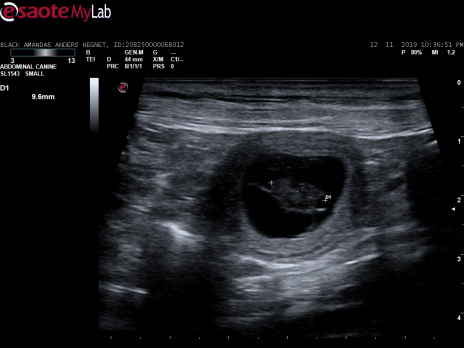

Scanningsbilleder fra den 12. november 2019

Black amandas Signed With Passioner i dag blevet scannet på Hinnerup Dyreklinik. Scanningen viste, at hun er meget drægtig.

Vi så mange fine små bobler, med hvert sit lille bankende hjerte

Herlighederne kommer til verden ca. den 20. december 2019.